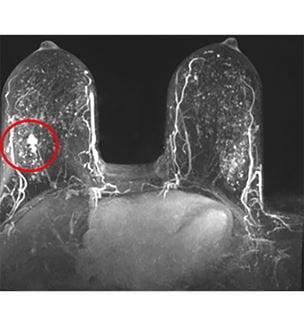

An Early Adopter of Abbreviated Breast MRI, UH Posts Noteworthy Early Results

Program has identified 19.9 breast cancers per 1,000 studies - Innovations in Cancer | Winter 2021